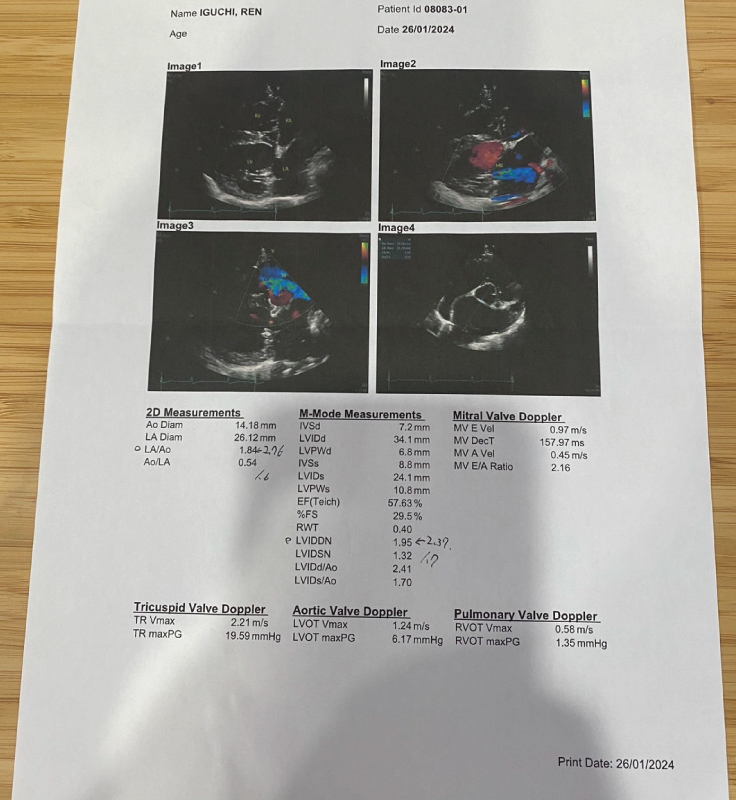

説明の中で最も驚いたのは、心臓の肥大していた

数値が小さくなったことです。

・左心房が手術前:2.76→1.84(正常値:1.6)

・右心房が手術前:2.37→1.95(正常値:1.7)

先生の見解としては、よくここまで肥大して

無事でしたね、頑張りましたね!と言って頂きました。